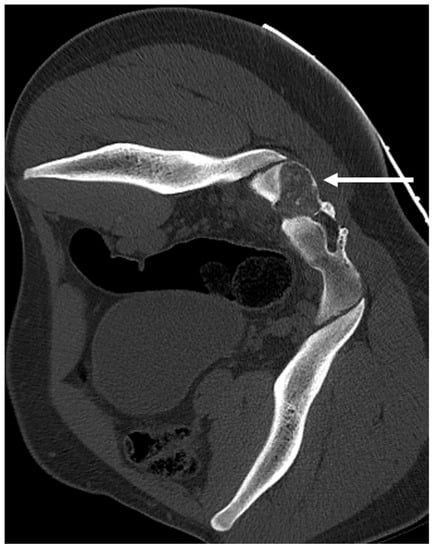

| Osteochondroma | Lesion continuity with cortex and medulla. | Cartilage cap |